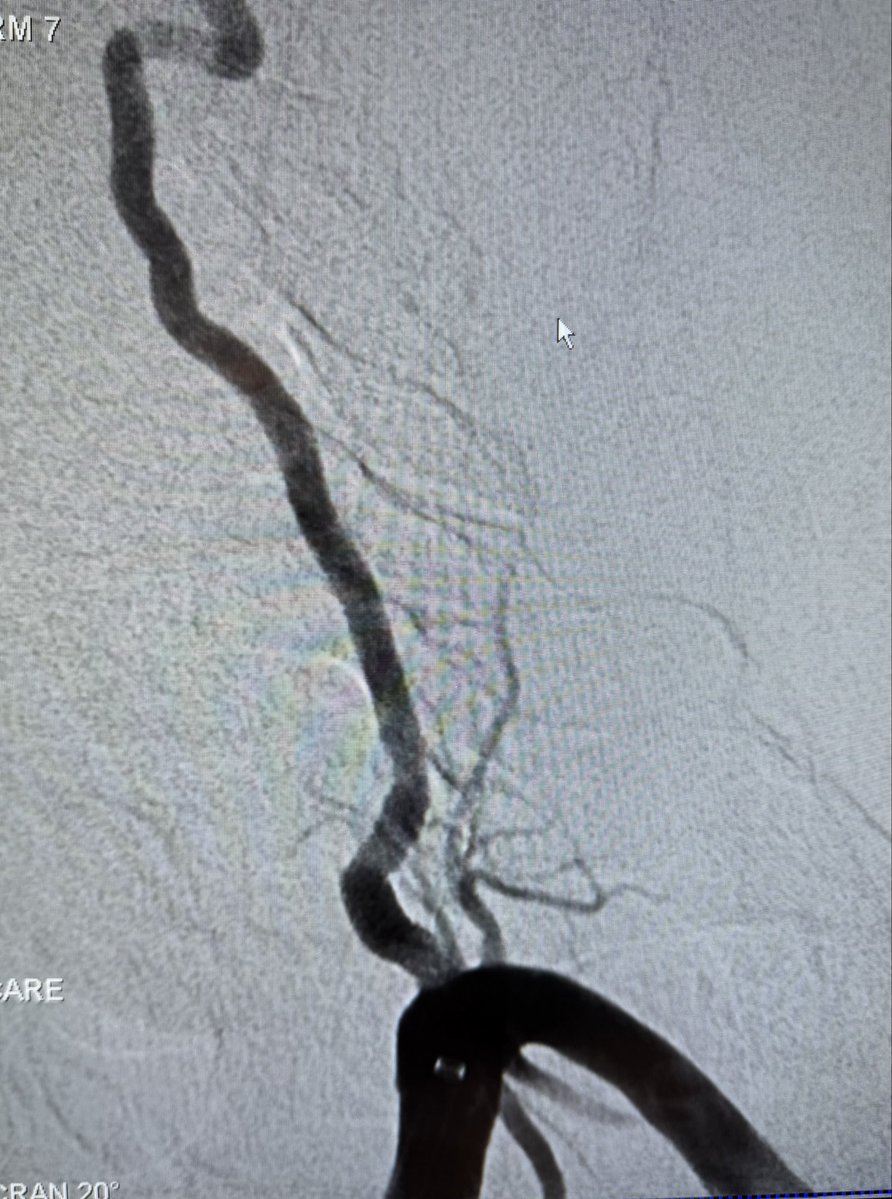

Partial disassembly at the junction to expose the internal stiff wire lets you manually control the lever and free a stuck Perclose footplate—turning a stressful moment into a controlled one. Practical, reproducible, and worth remembering.